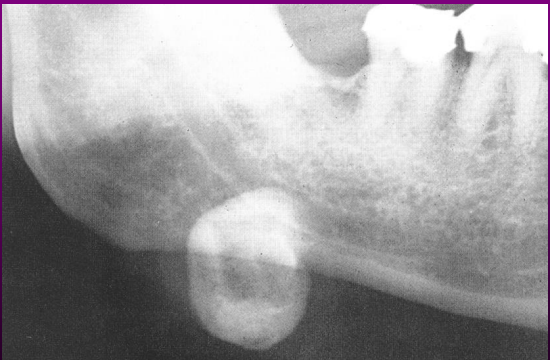

Osteoma Endosteal no Côndilo

Visualmente ele tem:

1)——- O**

2)——-L**

3)—-T*

4)—–D

A

*Alteração progressiva na oclusão do paciente.

*Desvio da linha média em direção ao lado afetado, má oclusão.

*Tumefação facial.

*Dor e limitação na abertura da

boca.

*Para distinguir hiperplasia condilar de osteomas:

os osteomas condilares são lobulados

hiperplasia do côndilo mantém sua forma original

Cementoblastoma Radiografia ?

* 2/3 dos pacientes apresentam dor intermitente de baixa intensidade e tumefação local. * Massa radiopaca que se funde a raiz de um ou mais dentes, circundada por fina halo radiotransparente. Contorno da raiz é perdido. *Fusão com a raiz do dente envolvido.